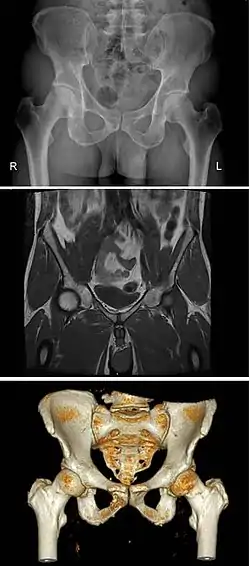

![]() Male type pelvis | |

![]() Female type pelvis | |